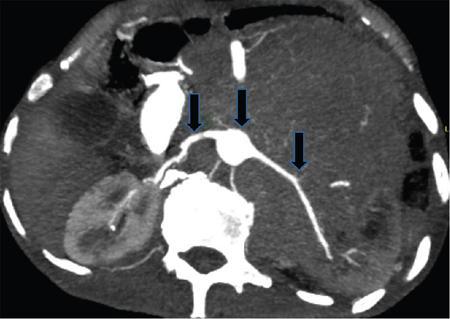

• Certain neoplasms tend to grow and spread in-between normal structures and encase vessels without causing luminal narrowing or compression. This is also known as a mantle growth pattern. Examples include lymphoma, lymphangiomas and ganglioneuromas. Lymphomas typically encase the aorta, IVC and major retroperitoneal vessels and displace the aorta anteriorly – this is known as the ‘floating aorta sign’ or the ‘CT angiogram sign’. Nonneoplastic diseases such as Erdheim–Chester disease and retroperitoneal fibrosis also present with mantle growth (Figs. 10.17.2.610.17.2.7).

Fig. 10.17.2.5 Mantle growth pattern – Axial CT angiogram in a 64-year-old male with DLBCL (diffuse large B cell lymphoma) shows the lymphomatous mass encases aorta and major retroperitoneal vessels (black arrows) by extending in between normal structures. Source: Authors own